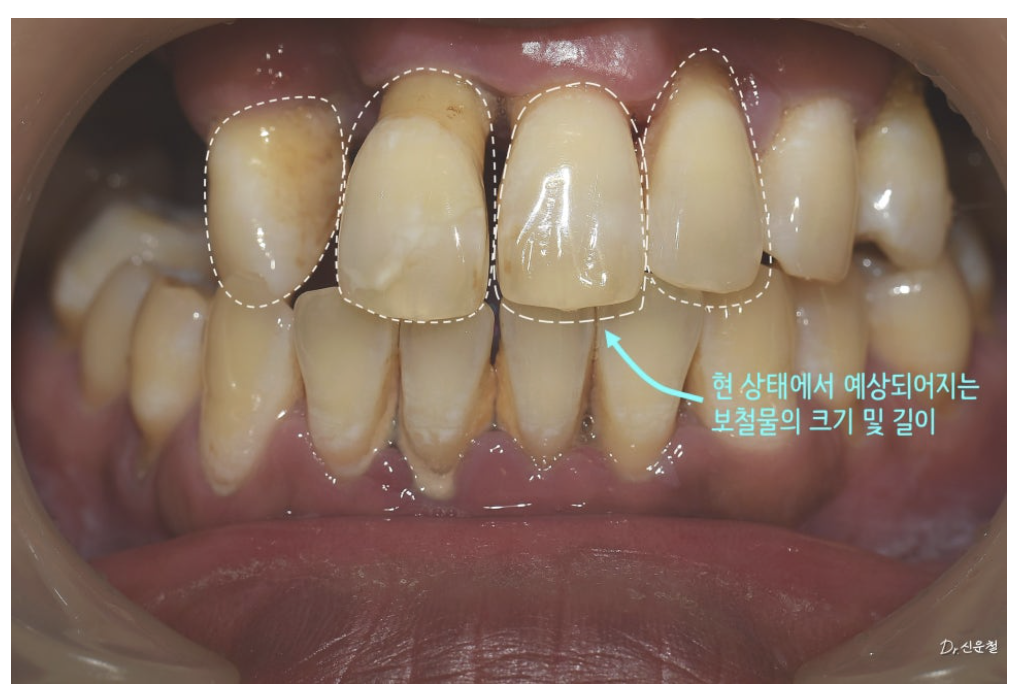

앞니는 일부 남아 있었지만

오랜 염증으로 인해 치아를 지지하던 뼈가 많이 흡수된 상태였습니다.

잇몸뼈가 줄어들면

잇몸은 함께 내려가고

내려간 잇몸은 다시 올라오지 않습니다

이 경우 보철물을 만들면

앞니가 길어 보일 수밖에 없는 구조가 됩니다.

앞니는 ‘치아 + 잇몸’을 함께 고려

임플란트 식립 후 보철 단계에서

특히 앞니는 더 신중하게 접근했습니다.

치조골이 전반적으로 내려간 상태였기 때문에

단순히 치아 색 보철물만 사용하면

앞니가 부자연스럽게 길어 보일 수 있었습니다.

그래서

치아 부분은 치아 색으로

잇몸이 있어야 할 위치에는 잇몸처럼 보이는 핑크 보철을 함께 표현해

자연스러운 인상을 만들었습니다.